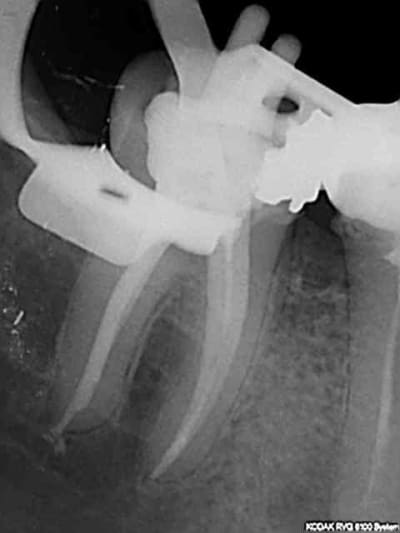

90 mn 2 molar endo + extrac 38. Un peu lent du à la difficulté à anesthésier (30 mn). les crochets apicaux traités comme si ils n'existaient pas avec le r25.

les 6 canaux avec le même r25. Attention toutefois je m'y suis repris à plusieurs reprises pour envoyer le s1 à l'apex (alternance r25 s1) et une bonne ouverture des entrées au largo ainsi qu'une très large cavité d'accès. Je n'ai à ce jour jamais cassé de r25, mais jamais essayé avec les plots en plastique .)

cela n'était pas des petites racines lt 24-25 mm. Big up à la digue qui m'a apporté un très gros confort de travail et m'a fait gagner du temps. Il n'y a que les imbéciles qui ne changent pas d'avis.